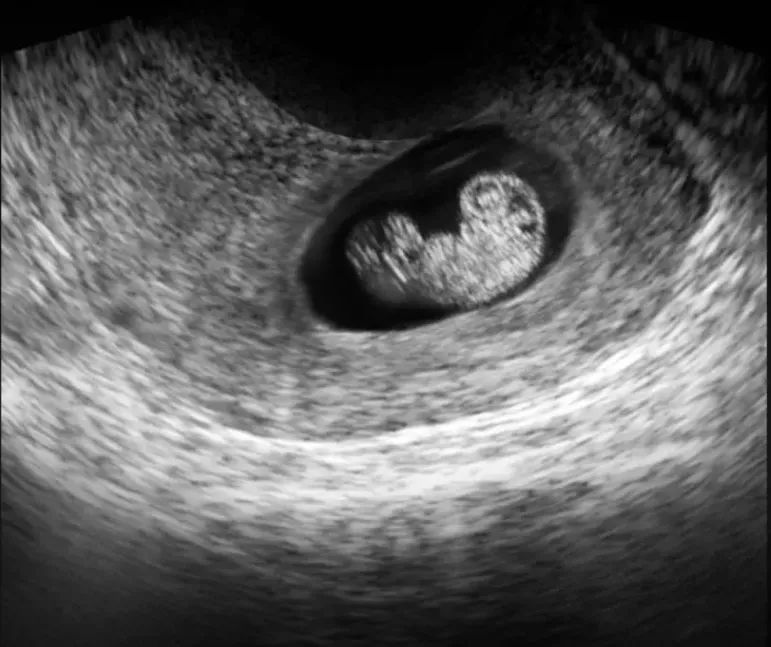

2.FE-胚芽

孕6-7周,胚囊内卵黄囊旁可以观察到胚芽。胚芽就是以后发育为胎儿的原始结构,一般来说观察到胚芽就可以见到原始心管搏动,即心跳。一般建议孕50天左右做首次超声检查,确认胚胎着床位置、胚芽和心搏等状态,排除宫外孕等情况。